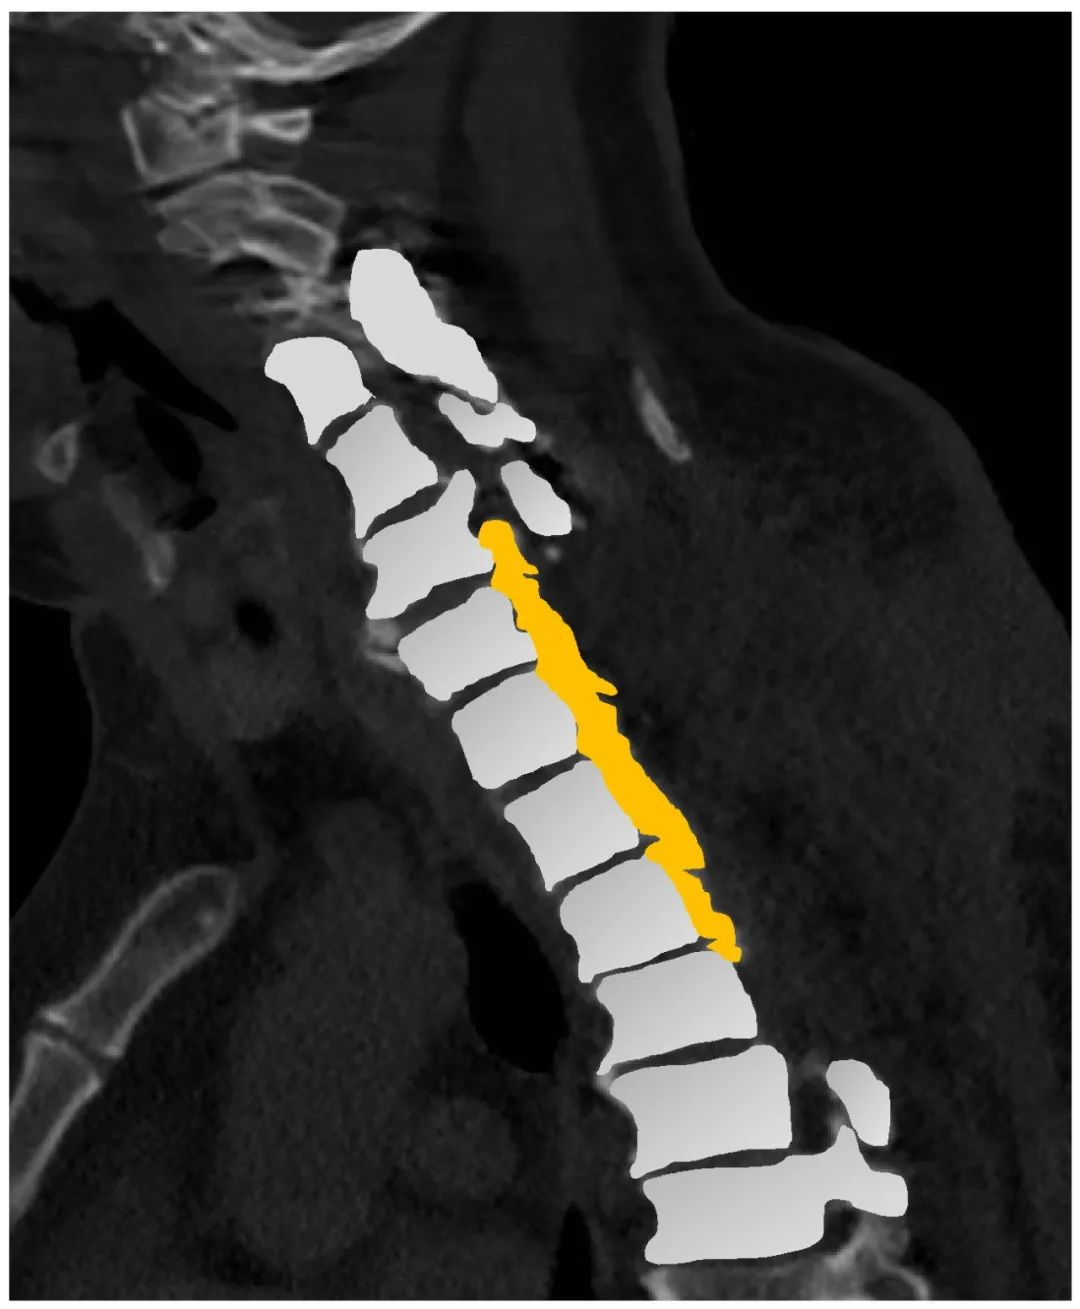

病史:M, 34 y/o

Numbness of right lower limb for 2 months, weakness for 1 week

Urination disorder

Body Weight: 120Kg; BMI: 39.5

影像资料:

Thoracic spinal stenosis(T2-T3)

Thoracic spinal stenosis decompression(T2-T3)